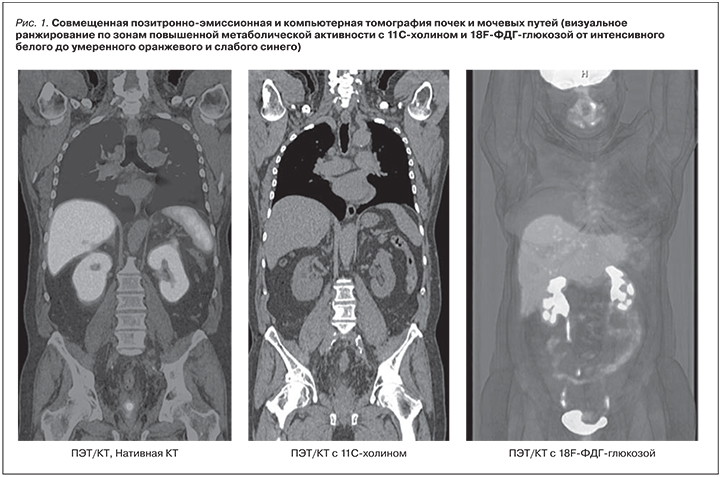

На рис. 1. представлены КТ- и ПЭТ/КТ-томограммы почек и мочевыводящих путей пациентов с применением различных РФП. Представленные данные позволяют сделать вывод, согласно которому ПЭТ/КТ-визуализация структурно-функционального состояния почек и мочевыводящих путей возможна и при этом достаточно информативна.